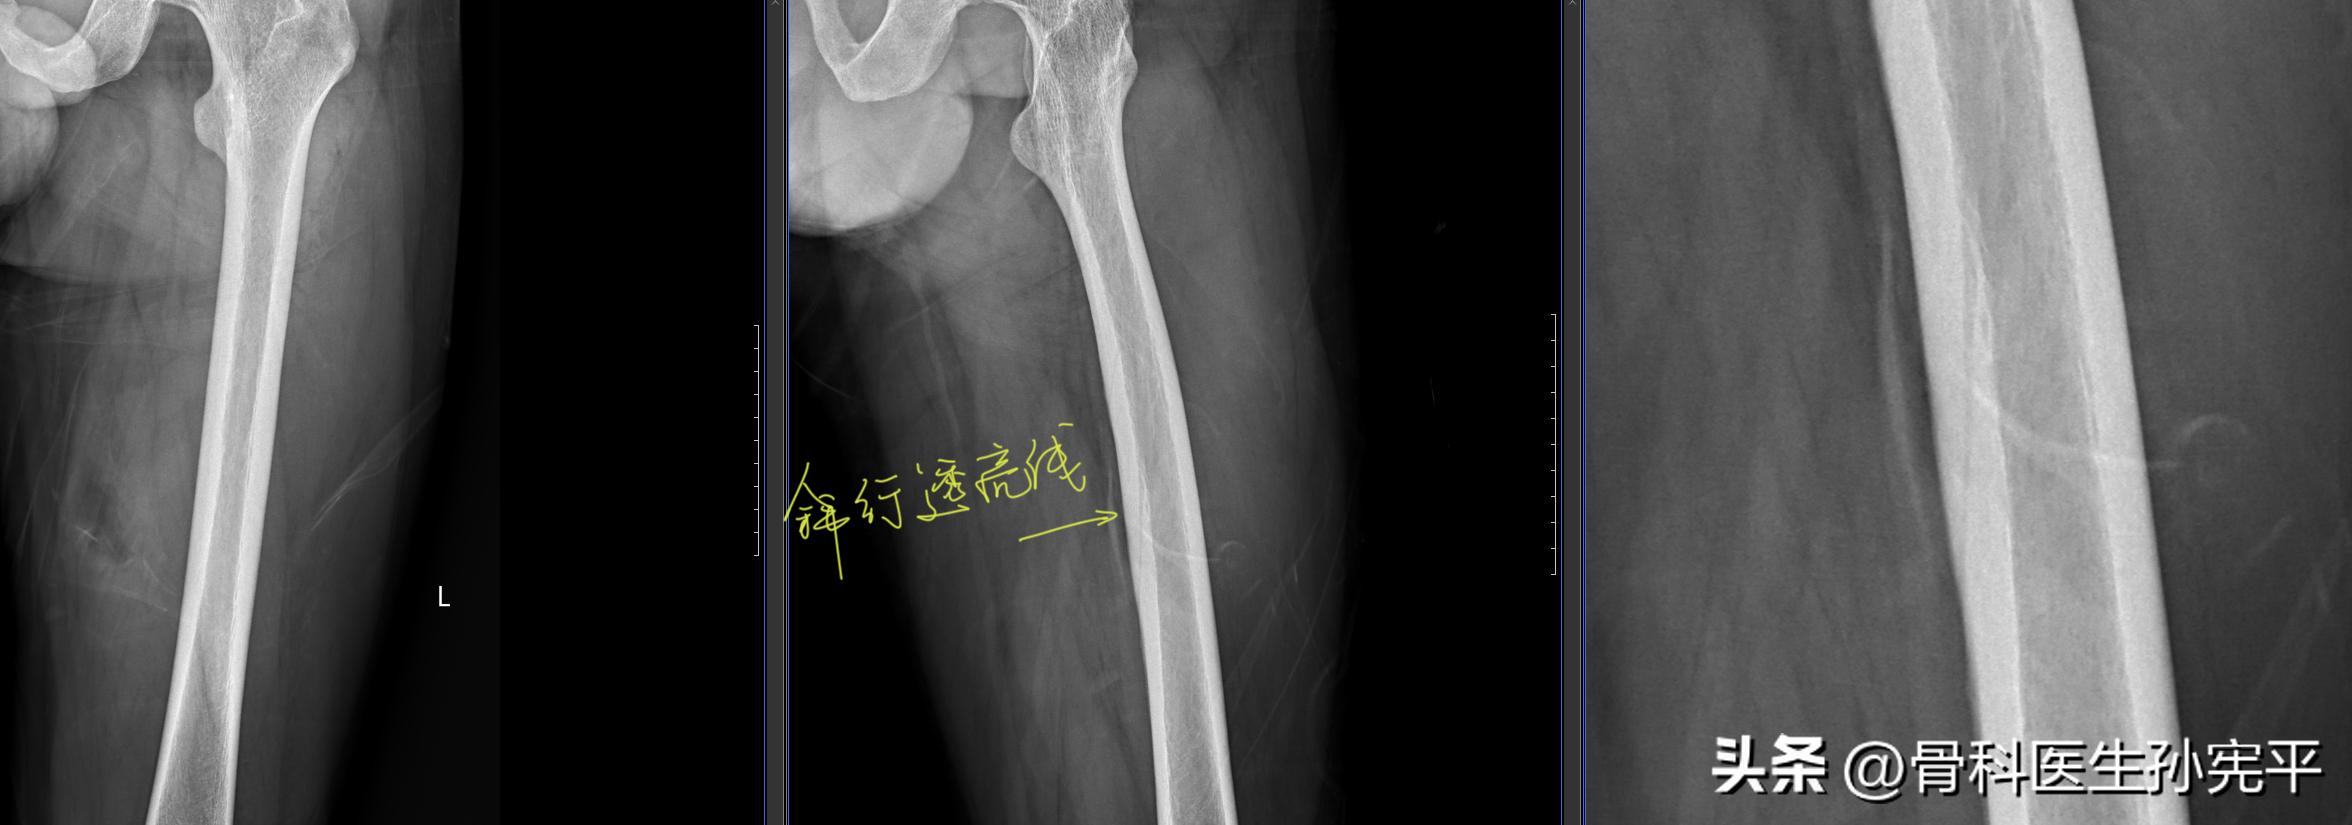

病例1:外伤后左大腿疼痛2小时。

左股骨滋养管影

阅片可见左股骨斜行透亮线,有些医生可能会将其误认为骨折线,其实这条斜行透亮线为骨滋养管影,为股骨干内斜行走向的透亮线,由皮质延伸至髓腔,边缘硬化、不锐利,可与骨折线向鉴别。